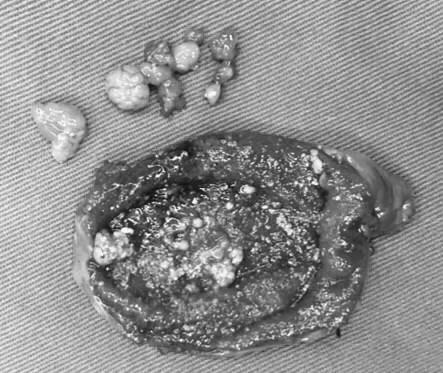

胆固醇性息肉(多发息肉)

胆固醇性息肉:胆固醇性息肉是最常见的胆囊息肉类型,占全部胆囊息肉样病变的85%左右。常表现为多发性,也可单发,息肉一般较小且增长缓慢。目前认为胆固醇性息肉不会癌变或癌变风险非常小。